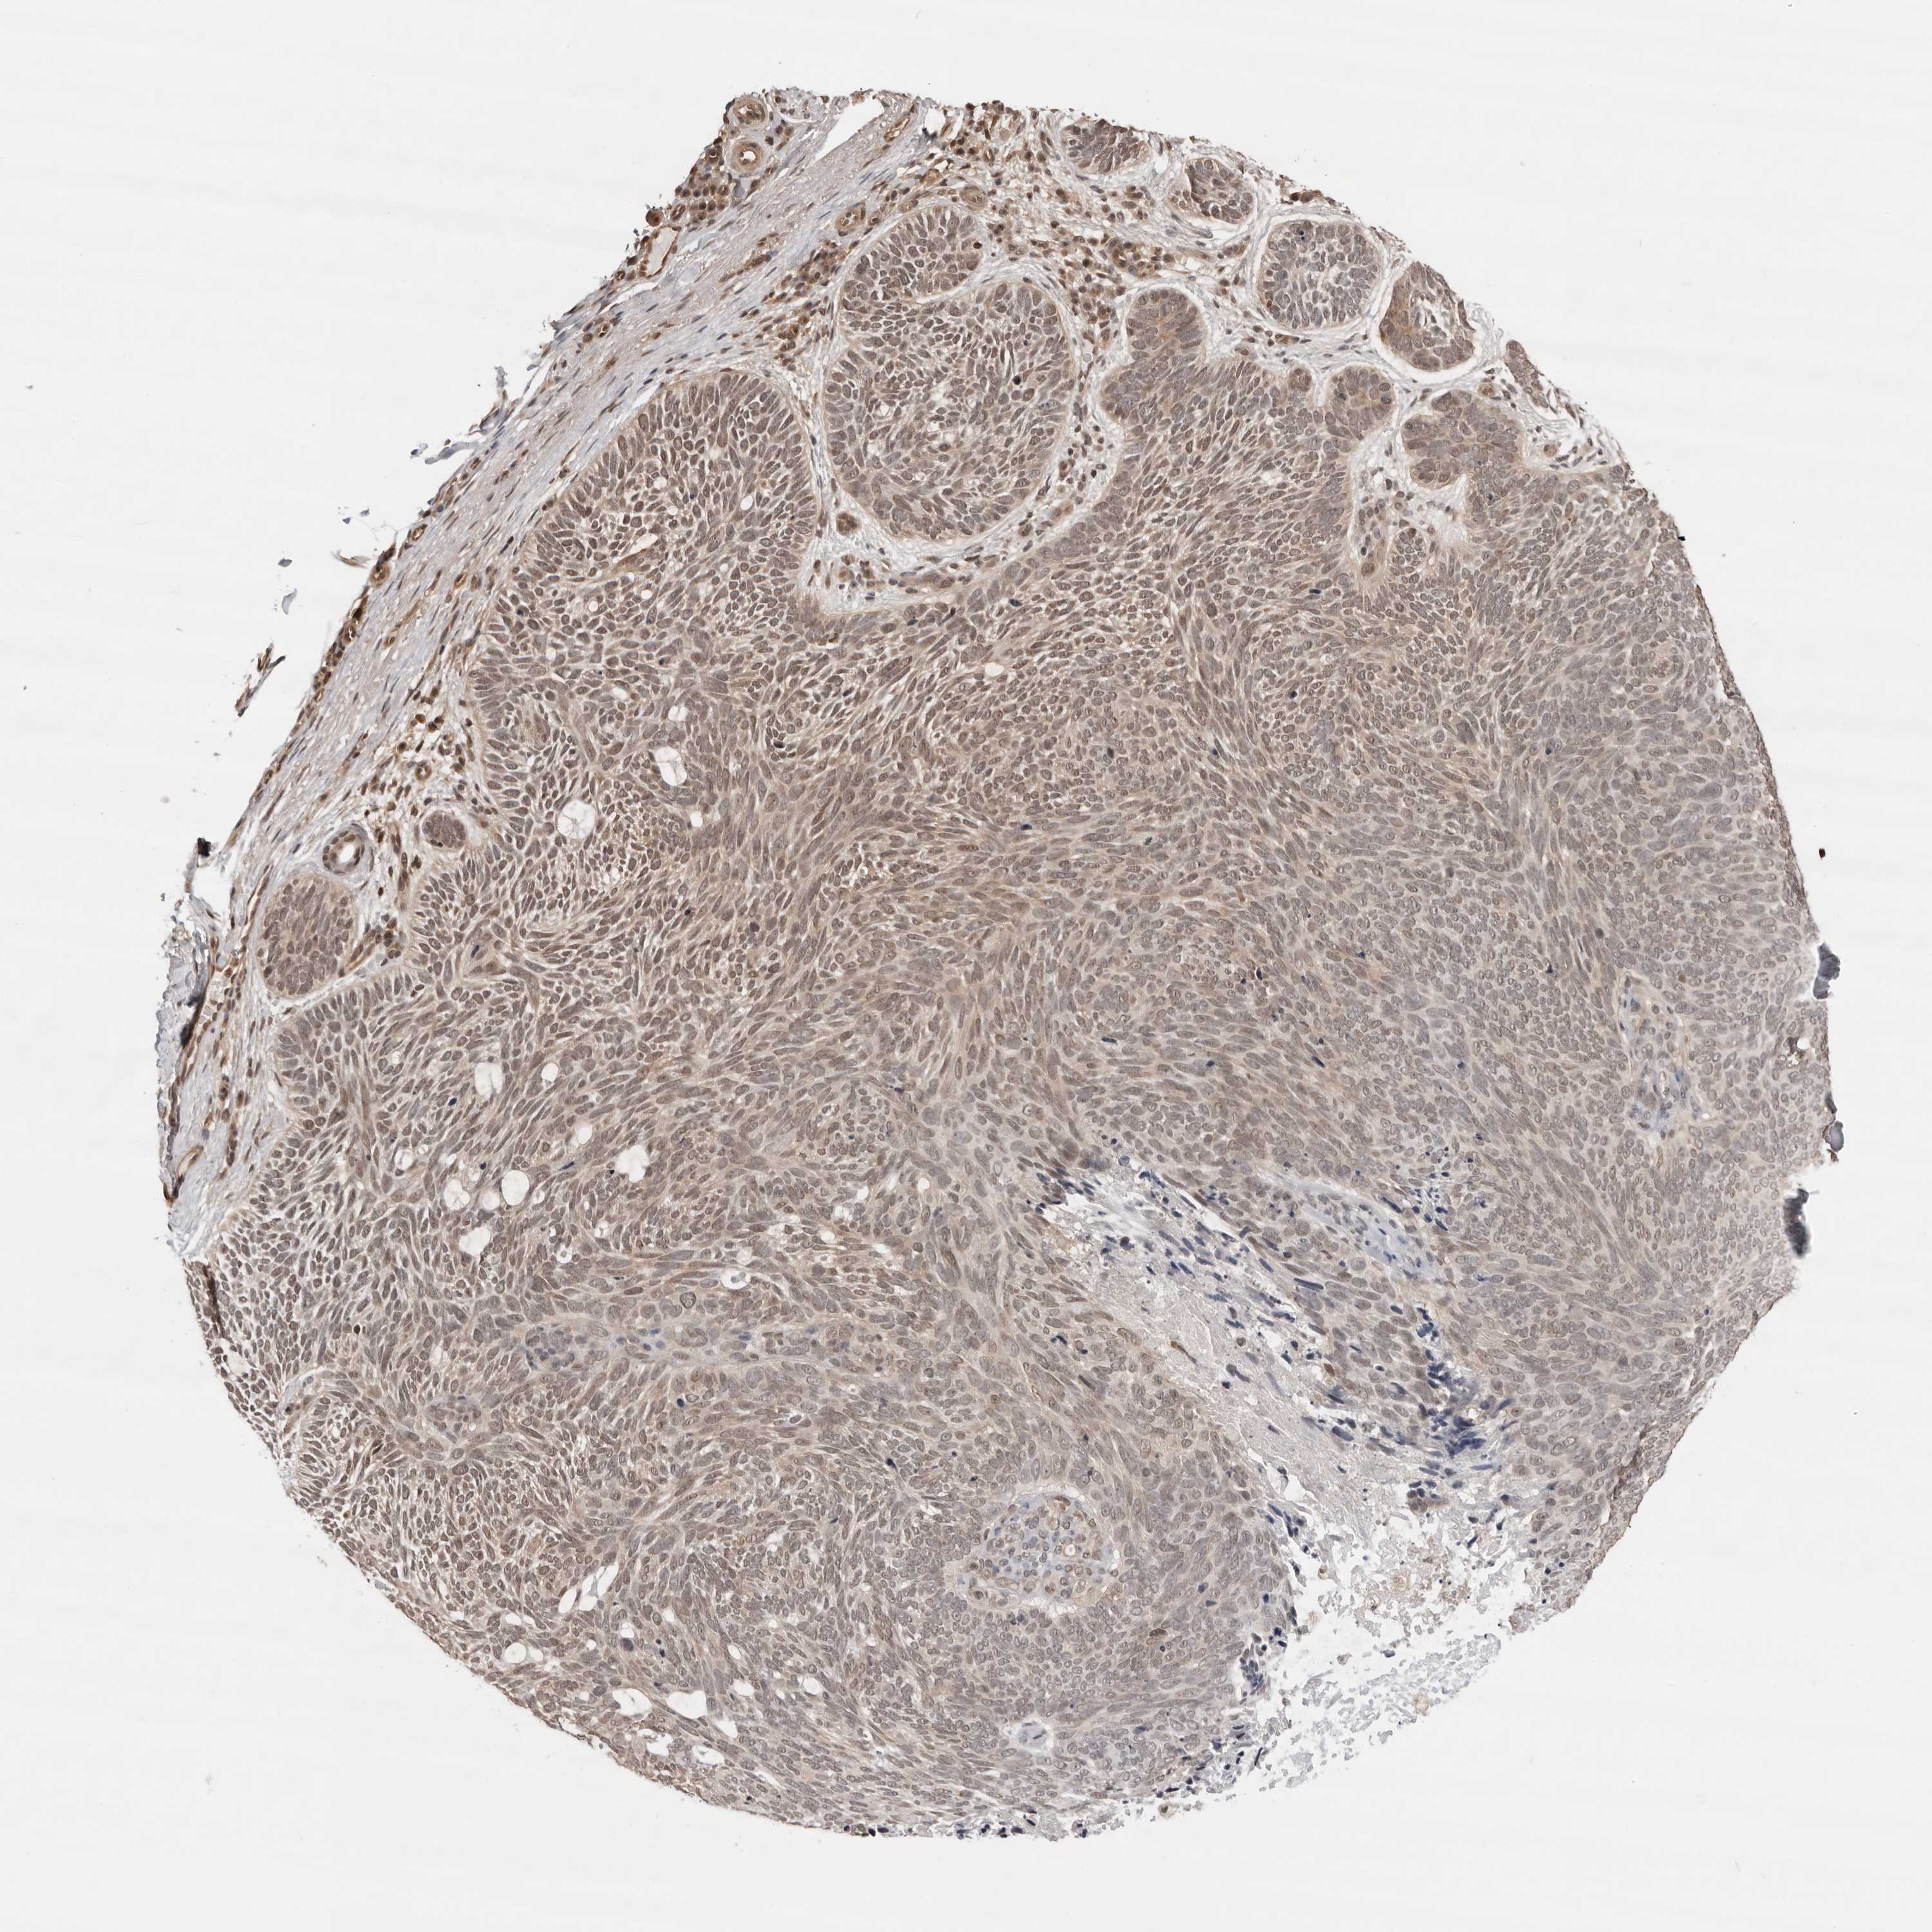

SKIN CANCER - Protein expressioni

A mouse-over function shows sample information and annotation data. Click on an image to view it in a full screen mode. Samples can be filtered based on level of antibody staining by selecting one or several of the following categories: high, medium, low and not detected. The assay and annotation is described here.

Each image is clickable and will lead to virtual microscopy that enables deeper exploration of all samples and also displays staining intensity scores, fraction scores and subcellular localization as well as patient and tissue information for each sample.

Antibody HPA031256

Staining

High

Medium

Low

Not detected

Intensity

Strong

Moderate

Weak

Negative

Quantity

>75%

75%-25%

<25%

None

Location

Nuclear

Cytoplasmic/membranous

Cytoplasmic/membranous,nuclear

Squamous cell carcinoma, metastatic, NOS

Squamous cell carcinoma, NOS